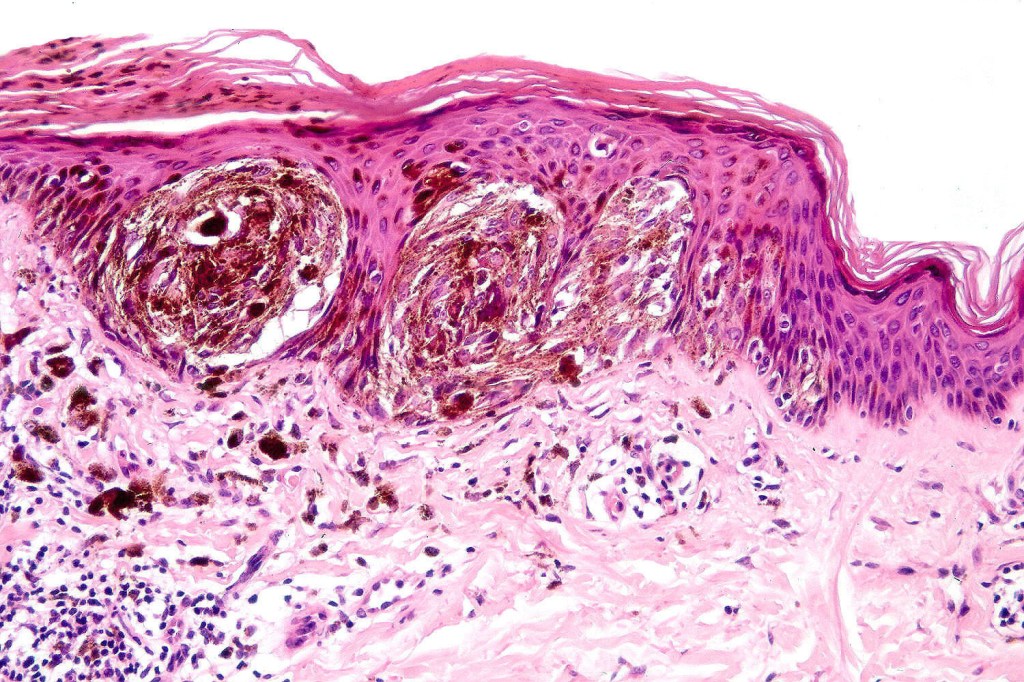

•Variant of Spitz nevus, readily identifiable at scanning magnification in the majority of cases

•Symmetrical and circumscribed with a characteristically flat lower border

•Vertically orientated oval junctional nests

. Heavy pigmentation although hypopigmented/amelanotic varinats can be encountered

•Acanthosis & hyperkeratosis

•Kamino bodies

. Lymphocytic infiltrate often seen at base